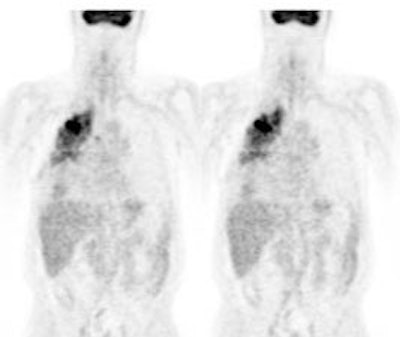

Response to treatment: 58 year old male with a left upper lobe non-small cell lung cancer and contralateral right hilar lymphadenopathy (blue arrow). FDG imaging also identified uptake in the inferolateral aspect of the right hemithorax which most likely represented a pleural metastasis with probable chest wall/rib invasion (black arrow). Because of the advanced stage of disease, the patient received radiation and chemotherapy. Follow-up PET FDG imaging demonstrated decreased tracer uptake and decreased size of the primary lesion in the left upper lobe (red arrow). The metastates in the right hilum, as well as the right pleura or chest wall have virtually resolved. Unfortunately, despite a positive response to treatment the presence of residual FDG activity in this patient would indicate a long term poor prognosis. Case courtesy of the North Texas Clinical PET Institute and CTI. |

|

Non-small cell lung cancer response to therapy: The patient shown below had widely metastatic left lower lobe lung cancer to mediastinal nodes, bones (left humerus), liver, and multiple pulmonary nodules. Note the dramatic improvement in the patient's post therapy scan (shown below). Click images to view rotating avi files. |